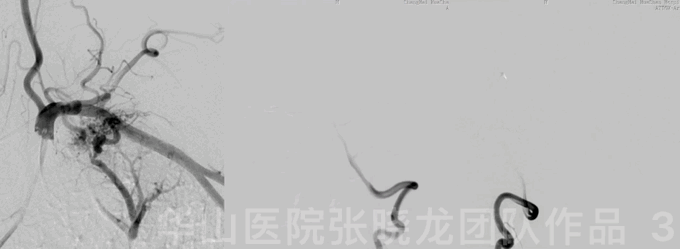

图 22 GIF. 术后6天复查造影,右侧小脑上动脉血流通畅,基底动脉瘤及左侧大脑中动脉瘤未见复发。此时脑梗后出血风险高于血栓风险,故抗血小板药物减至阿司匹林100mg+氯吡格雷25mg。